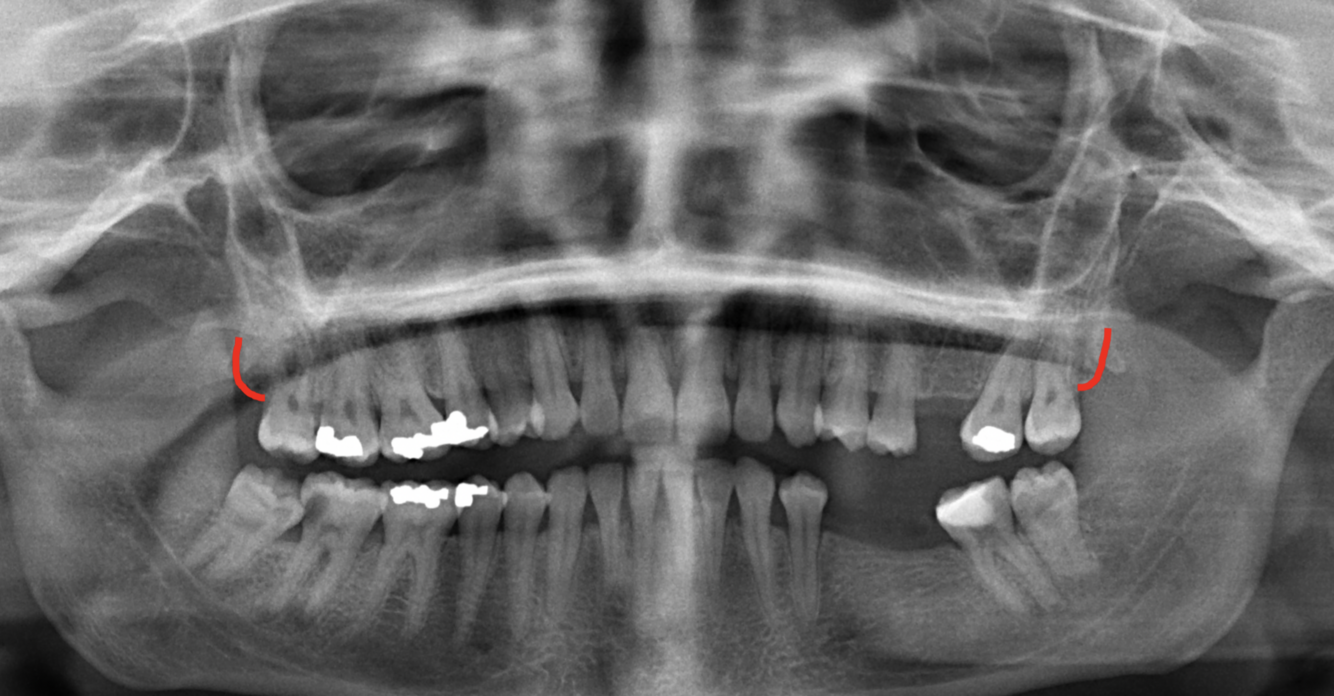

What is indicated by the red circles in the following image?

External auditory meatus